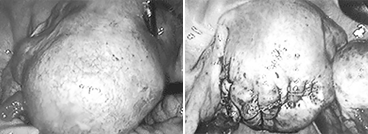

• 자궁내막증 수술

자궁내막증은 기능이 있는 자궁내막조직이 자궁이 외의 부위에 존재하는 만성 재발성 양성 질환으로 가임 여성의 10%, 난임 여성의 30%정도에서 발견됩니다. 진행된 중증의 자궁내막증은 난관폐쇄, 자궁부속기 유착 등을 일으켜 난관의 운동, 난관 내로의 난자 유입, 배란에 영향을 주어 난임의 원인이 될 수도 있고, 난포의 생성, 수정, 면역 및 착상에도 영향을 줄 수 있습니다. 또한 만성적인 하복부 통증과 심한 생리통 및 성교 시 통증은 삶의 질(quality)에도 심각한 영향을 줄 수 있습니다. 자궁내막증 진단의 최상의 방법은 복강경이며, 복강경을 통하여 자궁내막증 병변을 절제하거나 소작하고, 골반 장기의 유착을 제거하여 정상적인 골반구조를 회복할 수 있습니다.

또한 자궁내막증에 의한 난소 낭종을 제거함으로써 임신율을 높일 수 있고 통증을 경감시킬 수 있습니다. 수술 전후로 호르몬 치료를 3-6개월 정도 시행할 수도 있습니다.